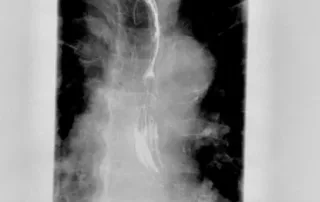

Contrast enhanced endoscopic ultrasound for the evaluation of lesions of the pancreas

The use of contrast during endoscopic ultrasound (CE-EUS) can [...]